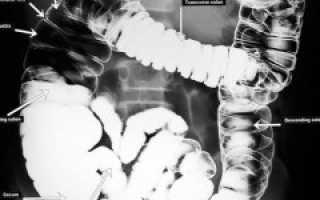

На нормальной рентгенограмме толстой кишки с двойным контрастированием форма и размеры органа остаются неизменными, не наблюдаются сужения или расширения просвета, а контрастное вещество равномерно распределено по стенкам. Складчатость слизистой оболочки соответствует норме.

После подготовки выполняется обзорная рентгенография органов брюшной полости. Затем в кишечник с помощью клизмы вводится контрастное вещество, и, меняя положение пациента (на боку, на животе, на спине, стоя), делают несколько дополнительных снимков. Последний снимок делается после опорожнения кишечника. При двойном контрастировании на заключительном этапе кишечник наполняется воздухом для получения изображений его внутренней поверхности.

После подготовки проводится обзорная рентгенография органов брюшной полости. Затем в кишечник вводится контрастное вещество с помощью клизмы, и выполняются дополнительные снимки в разных положениях пациента (на боку, на животе, на спине, стоя). Последний снимок делают после опорожнения кишечника. При двойном контрастировании на заключительном этапе кишечник наполняется воздухом для получения изображений рельефной внутренней поверхности.

Что можно увидеть на рентгеновских снимках кишечника с контрастом?

изменение просвета кишечника (сужение или расширение) и увеличение длины органа (удлинение толстого кишечника; значительное расширение просвета в области сигмовидной кишки);

изменение формы и положения кишечника;

наличие дефектов наполнения (мелкие опухоли в кишечнике; злокачественная опухоль, приводящая к сужению просвета восходящей ободочной кишки);

дефекты заполнения (указывает на выпячивания и углубления в стенках органа, куда проникает контрастное вещество; множественные дивертикулы);

наличие нескольких уровней жидкости в кишечнике, «чаши Клойбера» (скопления темного воздуха над жидкостью с горизонтальным уровнем светлого цвета — признак кишечной непроходимости).